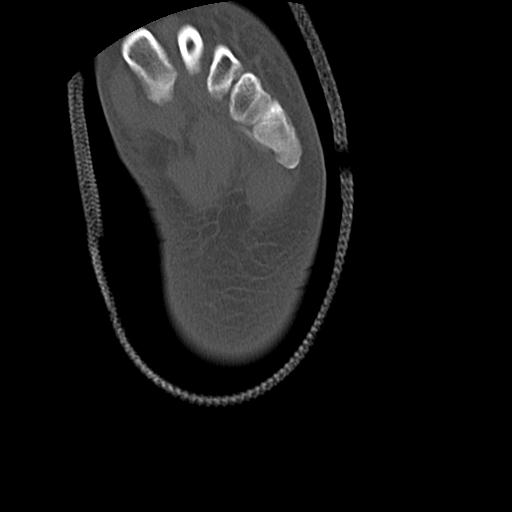

56476 8/28 4R 1/21 2R 左足関節 デジカメ写真 72歳女性 右足関節AS

102755 1/4 2R 1/15 2R 右足関節 68歳女性 右三果脱臼骨折

103177 3/11 右足 2R 3/16 右足 2R リスフラン脱臼 55歳男性